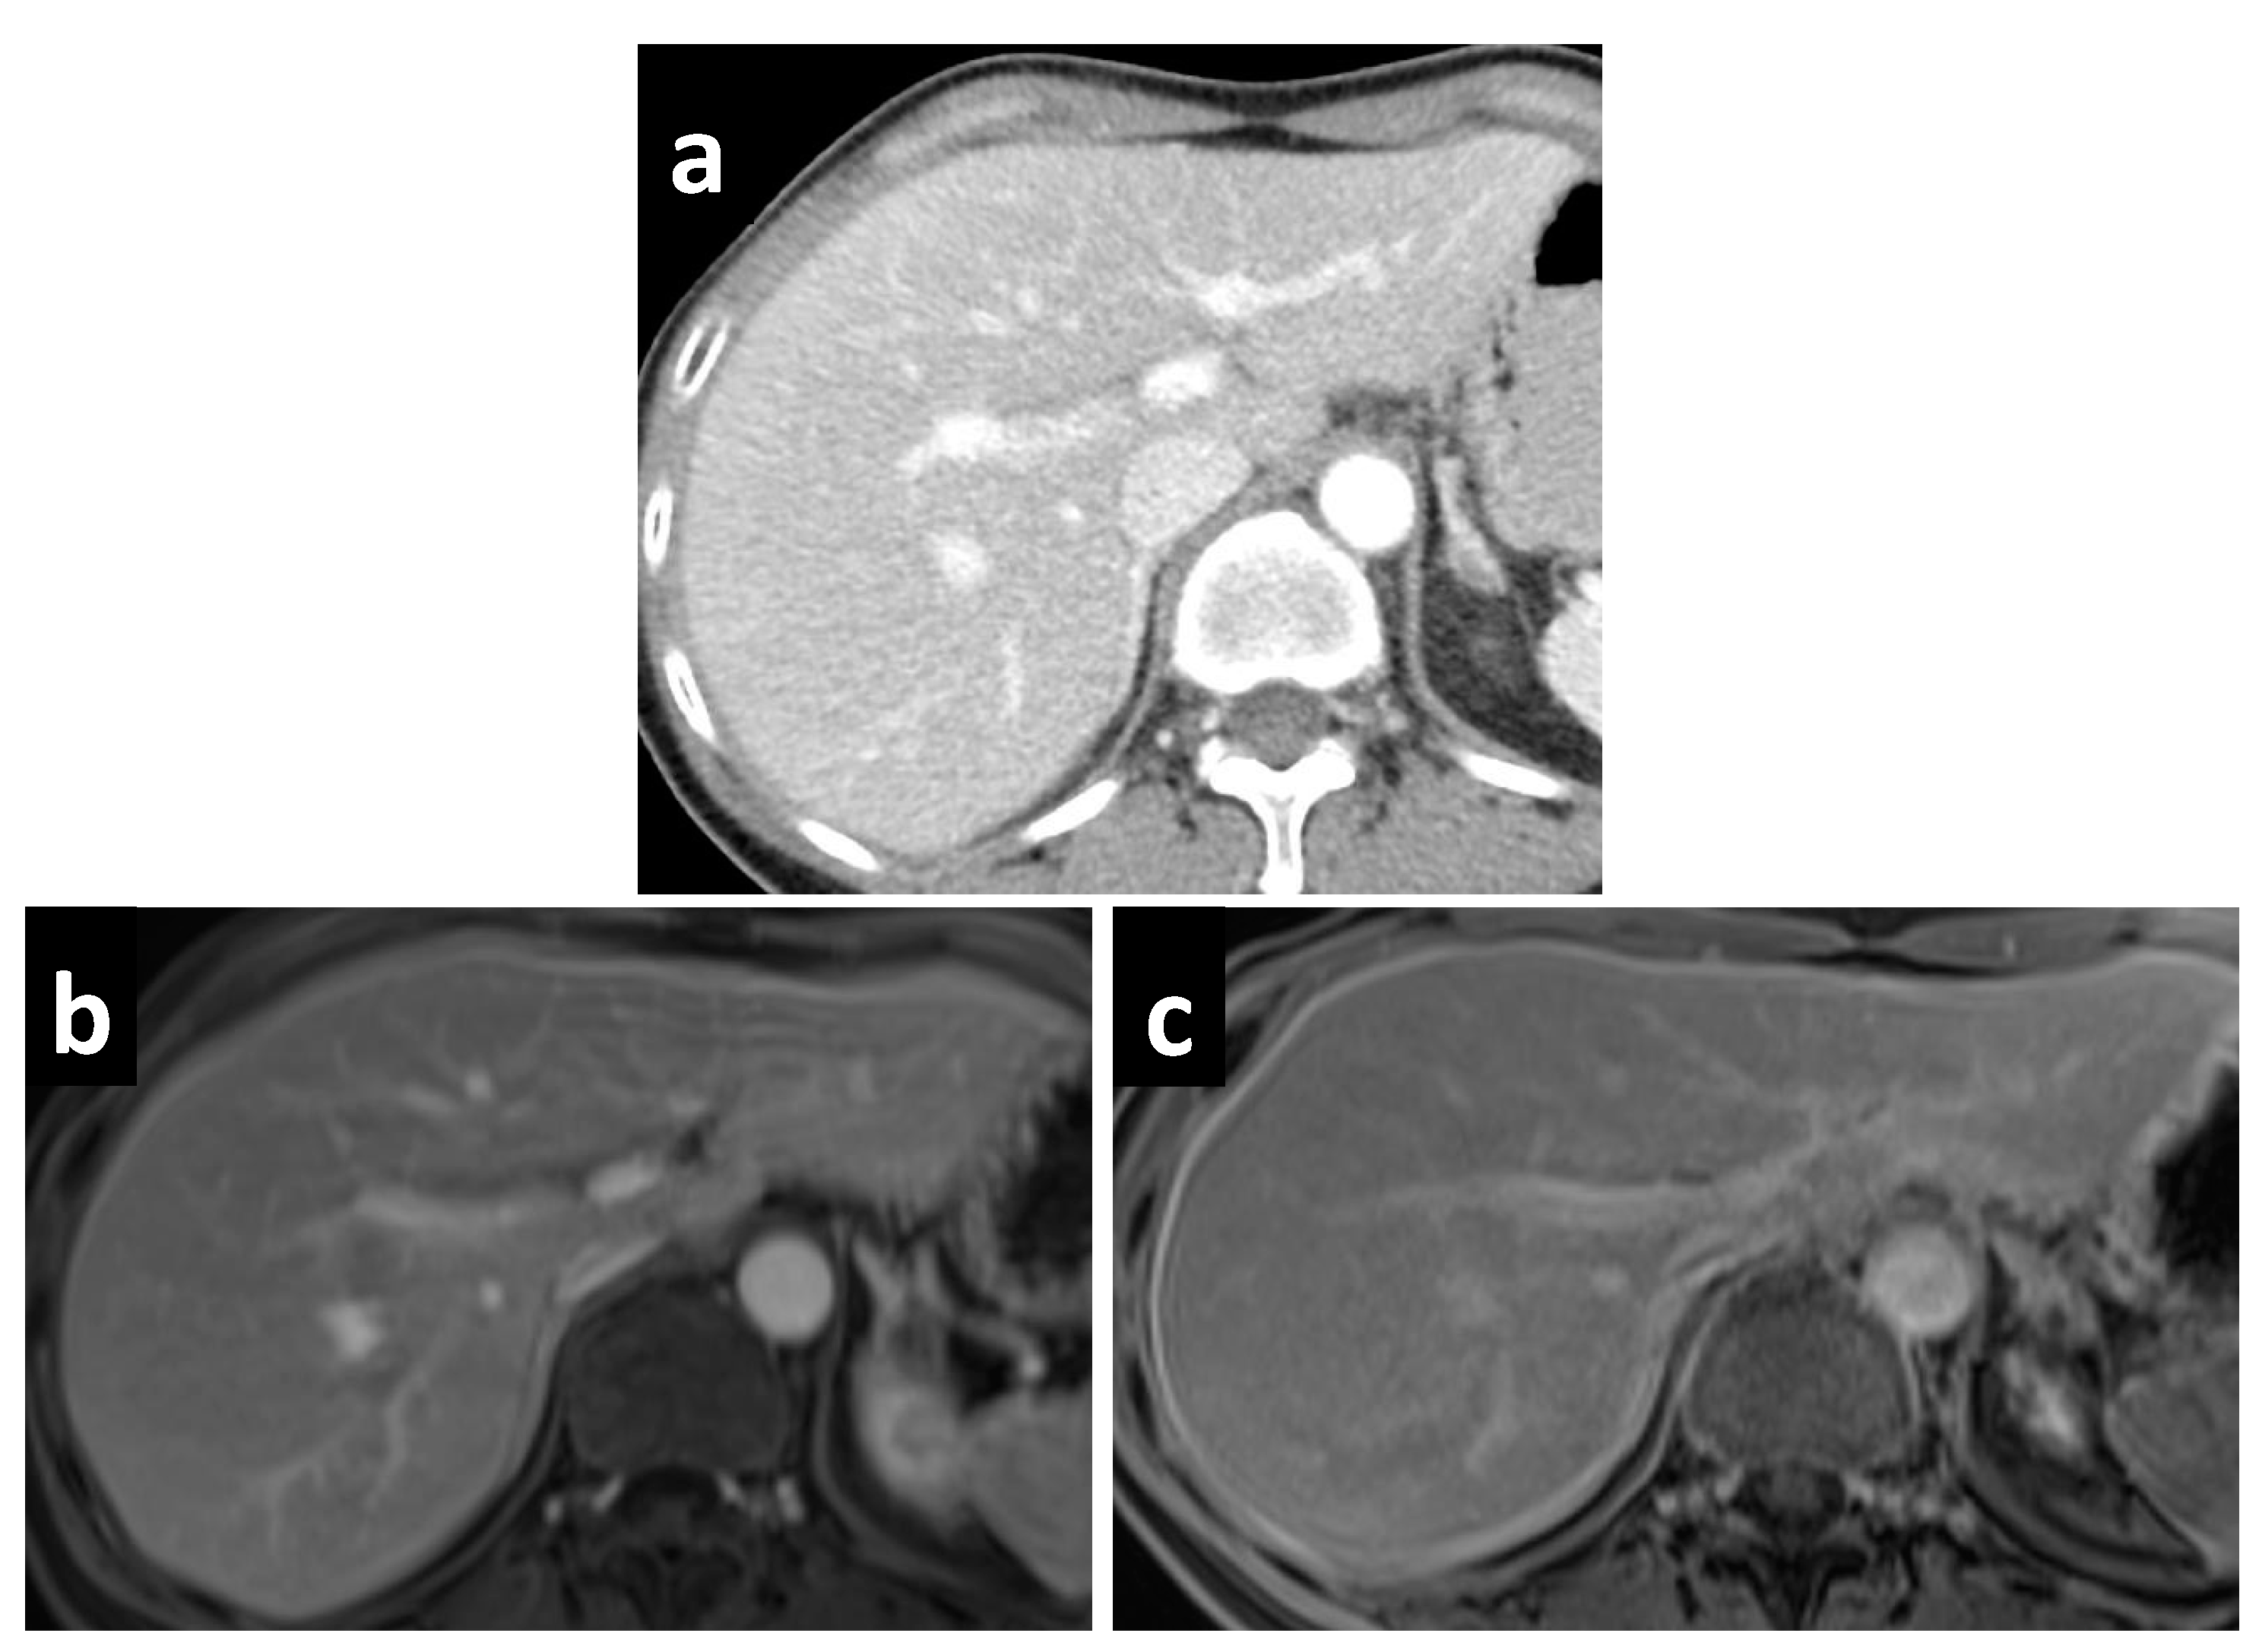

Figure 3.

A 61-year-old female with mucinous appendiceal neoplasm, a small amount of fluid is noted within the lesser sac on (a) CT and (b) T2W MRI. Enhancement within the fluid, however, is barely appreciated on the (c) portal venous phase of the MRI, but becomes clearly apparent on the (d) delayed MRI.